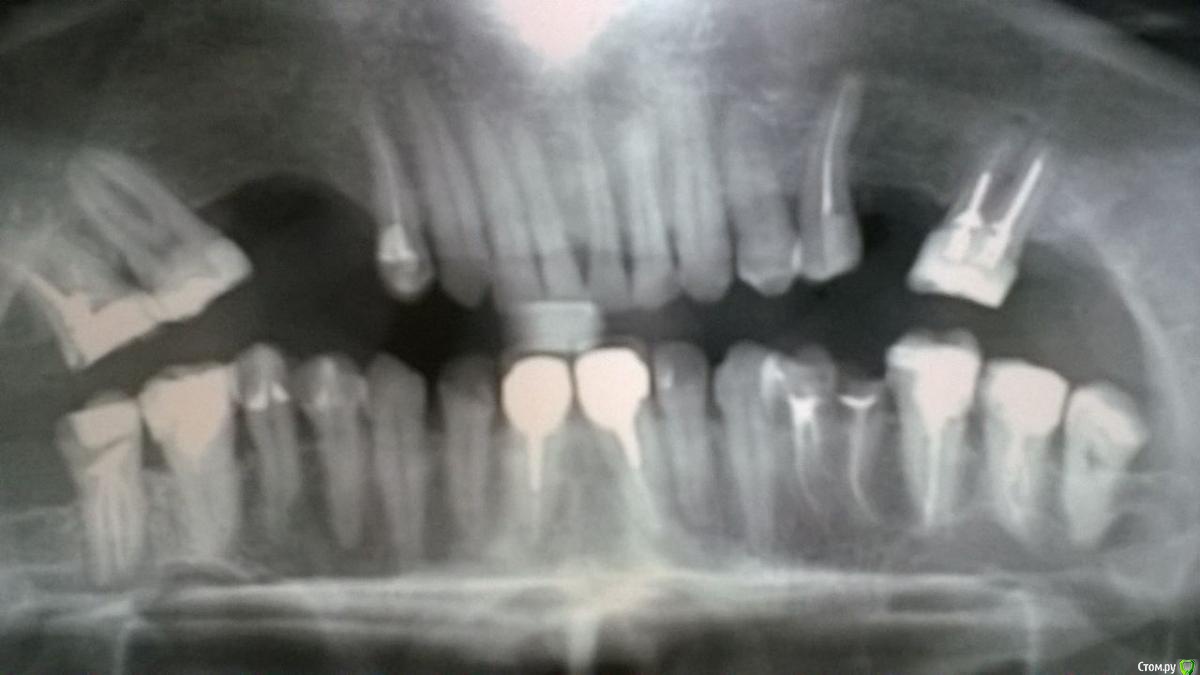

Денис79 Опубликовано 26 июня, 2018 Поделиться Опубликовано 26 июня, 2018 (изменено) Добрый день. Подскажите пожалуйста , собрался протезироваться, врач в клинике советует на моляры устанавливать литые металлические коронки, а не металлокерамику, а на остальные зубы металлокерамические коронки. Насколько это разумно решение, меня смущает что металлические коронки на молярах все равно видны при разговоре, может все таки настоять и попросить и на молярах тоже поставить металлокерамику? Заранее благодарю за ответ. Снимок прилагаю. Изменено 26 июня, 2018 пользователем Денис79 Ссылка на комментарий